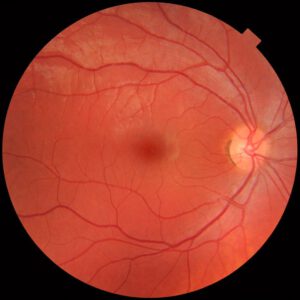

Conjunctivitis

Images

1